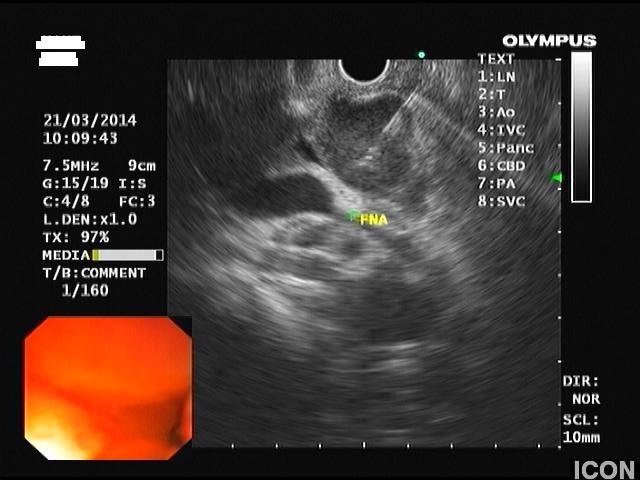

2) Αδενοκαρκίνωμα παγκρέατος

Άνδρας 68 ετών, χωρίς προηγούμενο ατομικό ή οικογενειακό ιστορικό, διαγνώσθηκε με σακχαρώδη διαβήτη από τον παθολόγο του σε εργαστηριακό έλεγχο ρουτίνας.

Στα πλαίσια διερεύνησης του πρωτοεμφανιζόμενου διαβήτη, υποβλήθηκε σε μαγνητική τομογραφία άνω κοιλίας (MRI/MRCP) που ανέδειξε μια συμπαγή μάζα στην κεφαλή του παγκρέατος, διαμέτρου περίπου 2εκ και μεγάλη διάταση του παγκρεατικού πόρου.

Ο ασθενής υποβλήθηκε σε ενδοσκοπικό υπέρηχο που έδειξε μια υποηχοϊκή μάζα διαμέτρου 21 χιλιοστών, με σαφή όρια, στην παγκρεατική κεφαλή και μεγάλη διάταση του χοληδόχου πόρου και του παγκρεατικού πόρου (διάμετρος 12 χιλιοστά).

Η μάζα είχε ξεκάθαρο διαχωριστικό όριο λίπους από την άνω μεσεντέριο φλέβα και δεν διηθούσε κανένα άλλο μεγάλο αγγείο της περιοχής (πυλαία φλέβα, σπληνοπυλαία συμβολή και αρτηρίες). Έγινε βιοψία με λεπτή βελόνη (FNA Χ3) και το κυτταρολογικό υλικό ήταν θετικό για αδενοκαρκίνωμα παγκρέατος. Το νεόπλασμα κρίθηκε χειρουργήσιμο και ο ασθενής υποβλήθηκε σε επέμβαση Whipple κατά την οποία αφαιρέθηκε πλήρως η παγκρεατική κεφαλή και ο όγκος σε υγιή όρια αλλά και 12 λεμφαδένες που ήταν όλοι αρνητικοί για κακοήθεια. Ο ασθενής υποβάλλεται σε συμπληρωματική χημειοθεραπεία.

Λήψη βιοψίας (FNA)